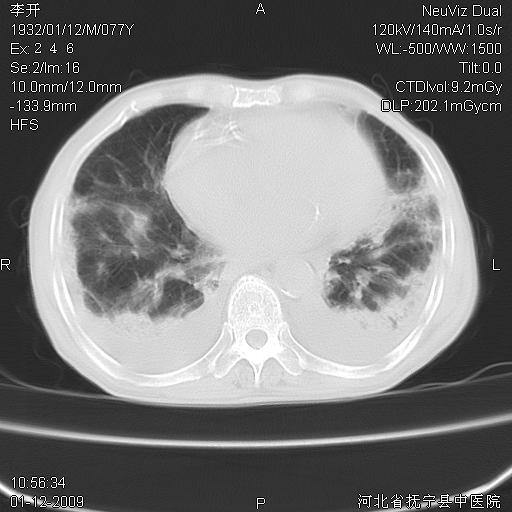

以下是引用黑白光影在2009-1-19 16:49:00的发言:[br]心衰肺水肿;心包、胸腔积液;冠脉钙化;肺部感染。